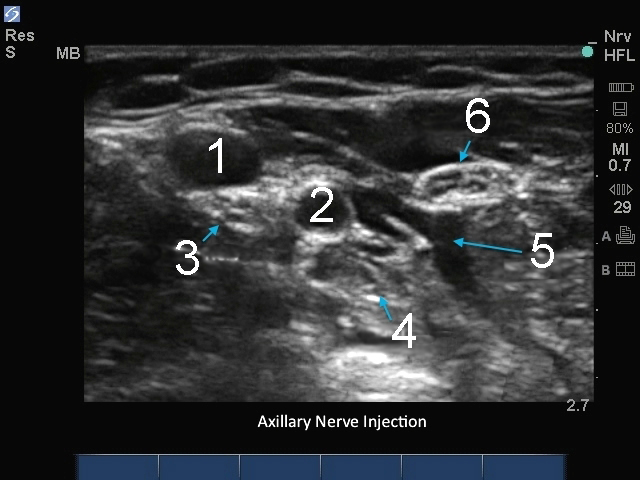

M-Turbo: Nervus axillaris nach der Injektion.

1. Vene

2. Arterie

3. Nervus medianus

4. Nervus radialis

5. Lokalanästhetikum

6. Nervus ulnaris